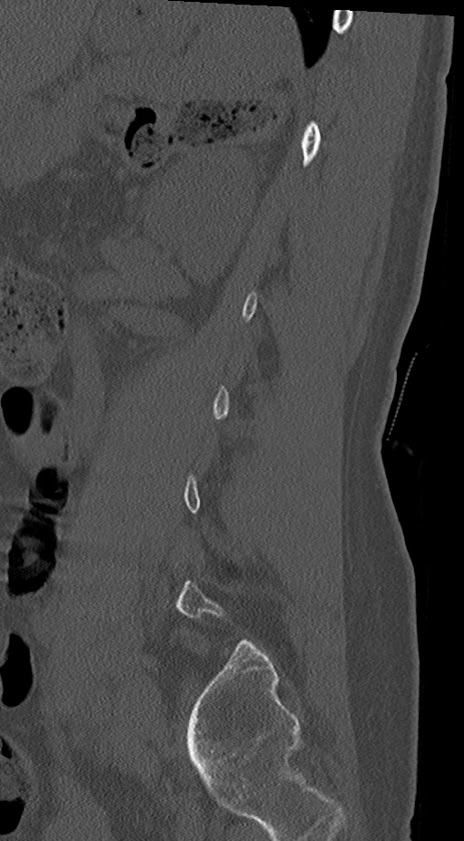

腰椎CT

冠状断像